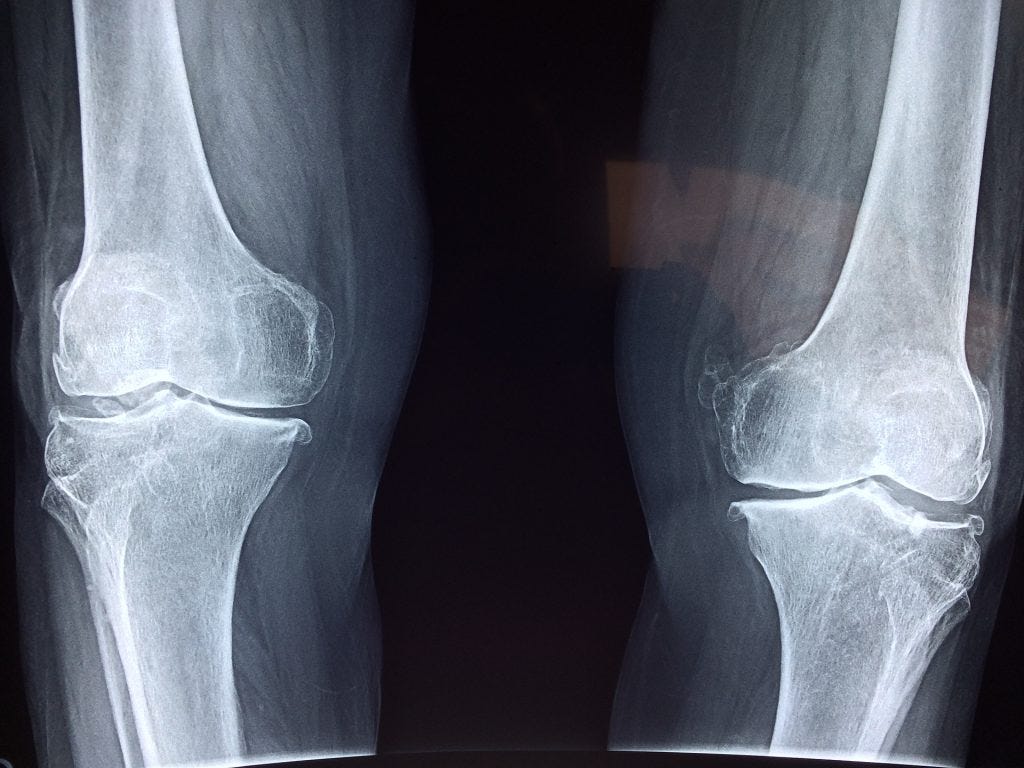

X ışını kamera. En basit şekliyle bir duvarında küçük bir delik bulunan karartılmış bir odadır. Dünyada ilk kez 2015 te kullanılan cihazın birinci versiyonu. Bir x ışını teleskobu xrt uzaktaki objeleri x ışını spektrumunda gözlemlemek için dizayn edilen teleskoptur. şiddetli kabızlık tedavisinde kolonu etkileyen sağlık problemlerinin tedavisinde kanser taramaları öncesinde doktorunuz tarafından önerilebilir.

en cok satan tibbi urunler x ray tibbi yazici x ray kamera tibbi x isini termal film yazici iyi fiyat ile buy tasinabilir x isini film yazicisi x

kore evet rayme x ray kamera evet biyoteknoloji dis rontgen unitesi dis tasinabilir x isini unitesi buy dis x ray kamera evet biyoteknoloji dis